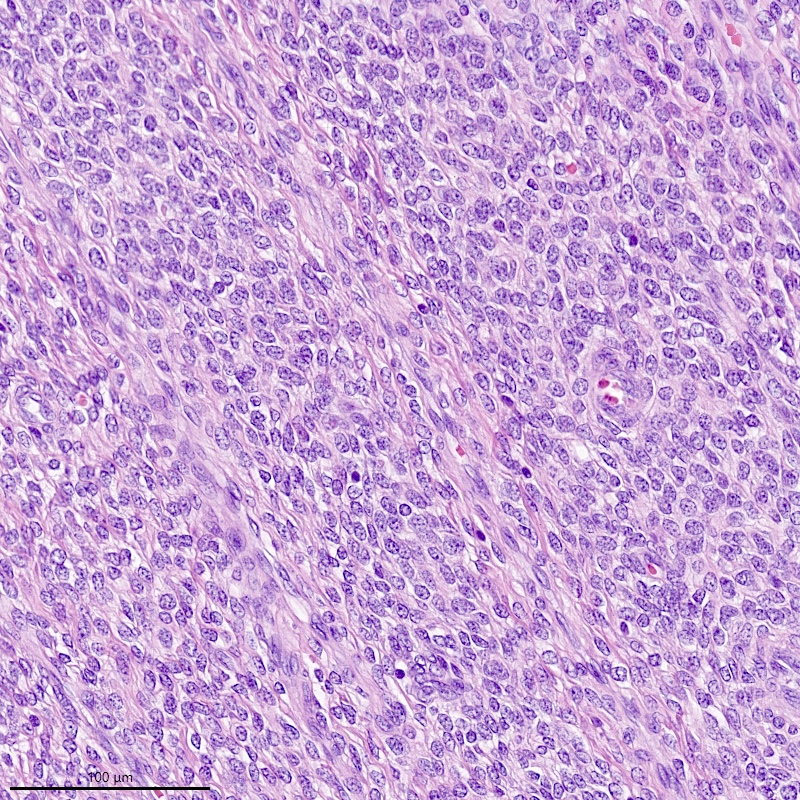

Microscopic (histologic) description

- Irregular cellular islands, forming permeative tongue-like pattern of myometrial invasion with frequent vascular invasion

- Monotonous oval to spindle cells with minimal cytologic atypia, vesicular chromatin and scant cytoplasm

- Mitotic count is usually low (< 5/10 high power fields), necrosis is usually absent

- Tumor cells may whorl around delicate arteriolar type vessels, reminiscent of proliferative phase endometrial stroma

- May have admixed collagen bands / plaques and foamy histiocytes

- May have smooth muscle differentiation, particularly in a starburst morphology, with collagen bands radiating towards the periphery of the nodule

- Other reported types of differentiation: fibromyxoid / fibrous, sex cord-like, epithelioid, rhabdoid, endometrioid glands, pseudopapillae, clear cells, bizarre cells, adipose tissue (Mod Pathol 2016;29:S92)

Microscopic (histologic) images

Contributed by Elizabeth Kertowidjojo, M.D., Ph.D., M.P.H. and Ayse Ayhan, M.D., Ph.D.